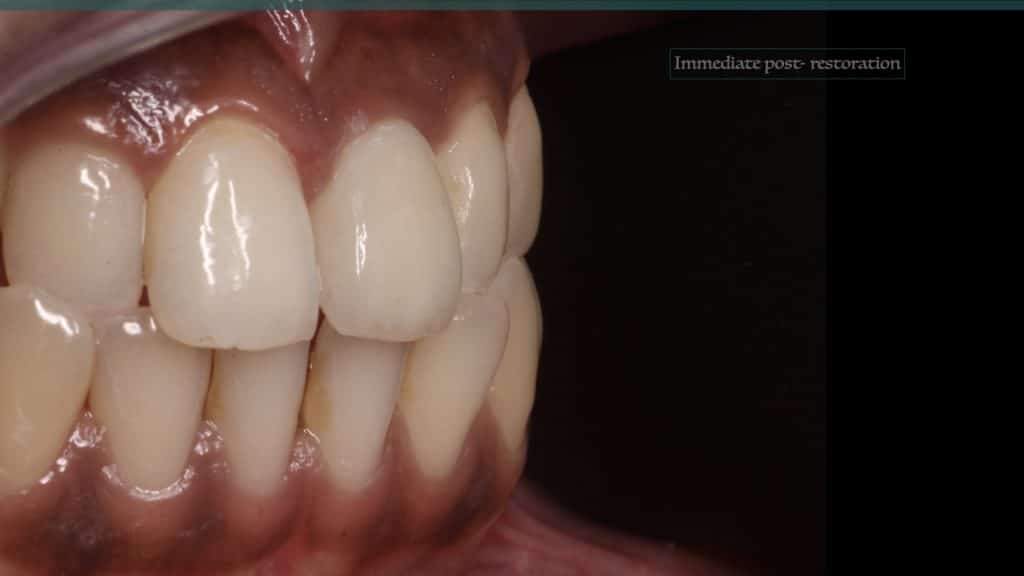

A 27-year female patient with dislodged Resin bonded FPD. She had that FPD for past few years, it had metal wings on palatal surfaces of UR1 and UL2 and a post like metal extension into the root canal of UL1. There was gingival abscess due to fractured root segment most probably due to extended metallic post like structure. Immediate implant placement (IIP) and Immediate restoration (IR) was planned for this patient.